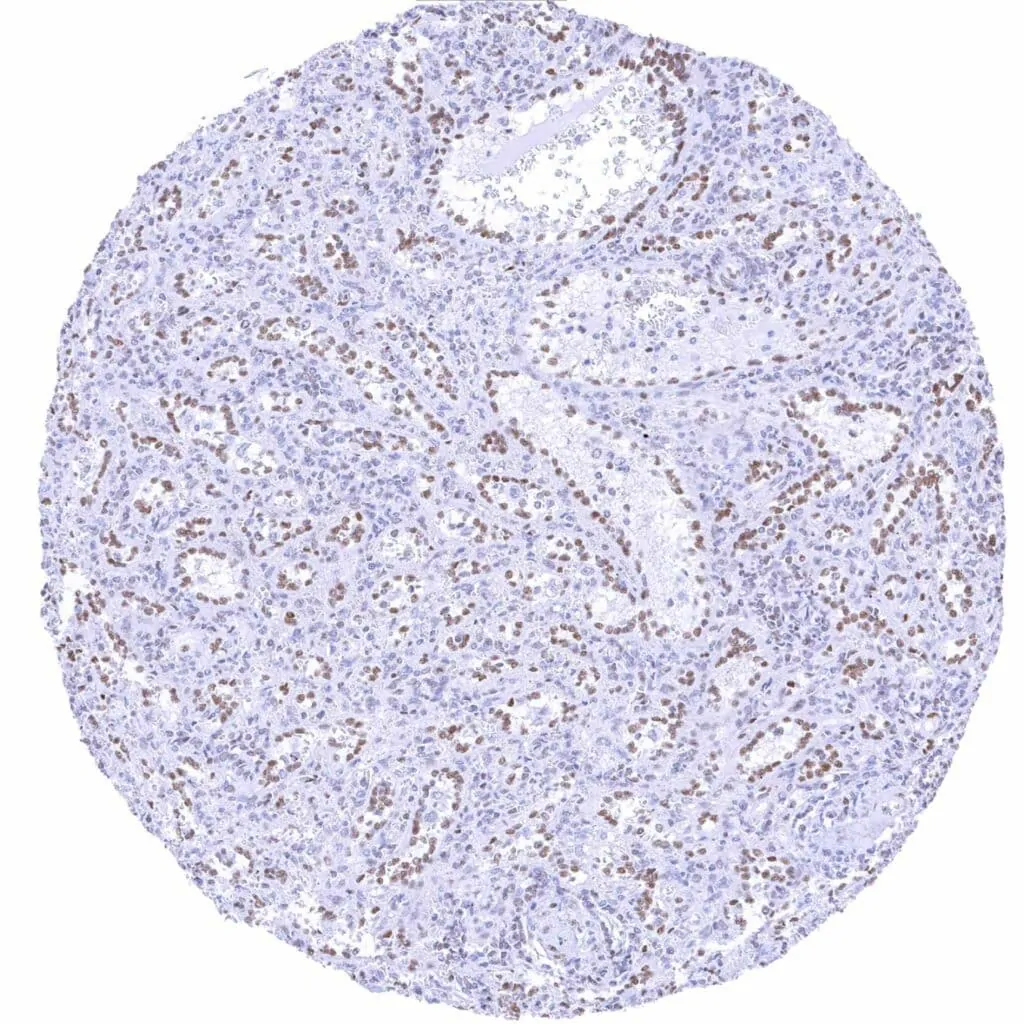

Bone marrow – Weak to strong TLE1 positivity of a significant fraction of cells-1